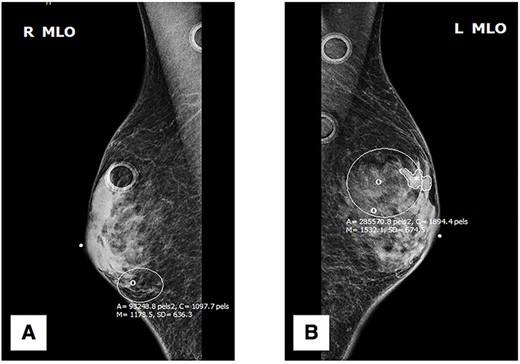

Initial physical exam was notable for bilateral gynecomastia with expression of scant serous fluid on palpation. Negative findings included any ‘active nipple’ discharge, presence of bleeding, breast tenderness, palpable masses or architectural abnormalities. The patient was referred for further diagnostic workup, beginning with digital mammography. Standard craniocaudal (Fig. 1) and mediolateral oblique (Fig. 2) views of bilateral breasts were performed, which revealed pleomorphic calcifications in the upper outer quadrant of the left breast, as well as amorphous calcifications in the lower inner quadrant of the right breast, consequently affording the patient a Breast Imaging Reporting and Data System score of 4 (suspicious for malignancy) with recommendation for subsequent biopsy.

Mediolateral oblique (MLO) mammography: (A) right breast; (B) left breast.